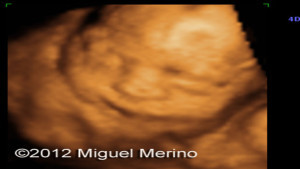

Ultrasonografías Varias

Envíado por Dr. Miguel Ángel Merino Araujo